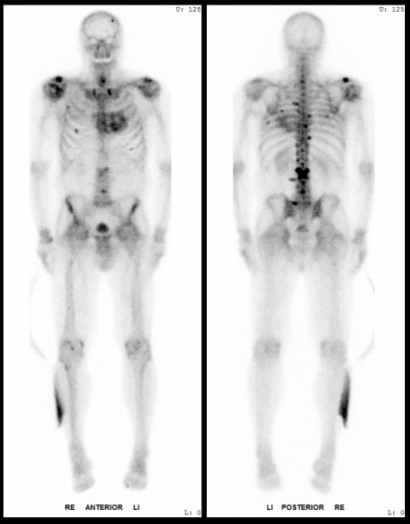

Bildergalerie (5 Bilder)

1 (Bild 1 von 5) Vorwärts »

« Zurück 5 (Bild 5 von 5)